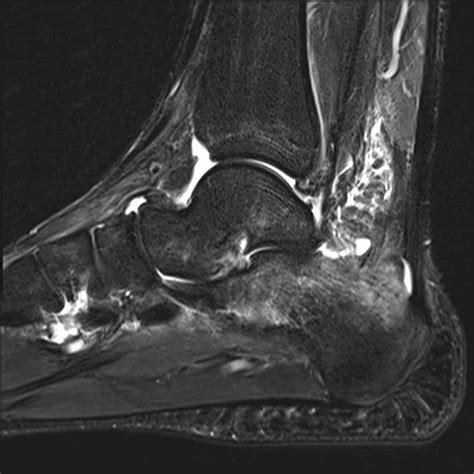

The syndrome was historically characterized in older women who chronically suppress their cough. By holding in their coughs to maintain social etiquette, these individuals inadvertently allow mucus, bacteria, and debris to accumulate in the airways of the lungs, specifically the right middle lobe and the lingula (part of the left upper lobe). This stagnation creates the perfect environment for NTM to colonize and cause chronic disease.

• High-Resolution Computed Tomography (HRCT) Scans: This is the gold standard for visualizing the characteristic bronchiectasis and nodules in the middle lobe and lingula.